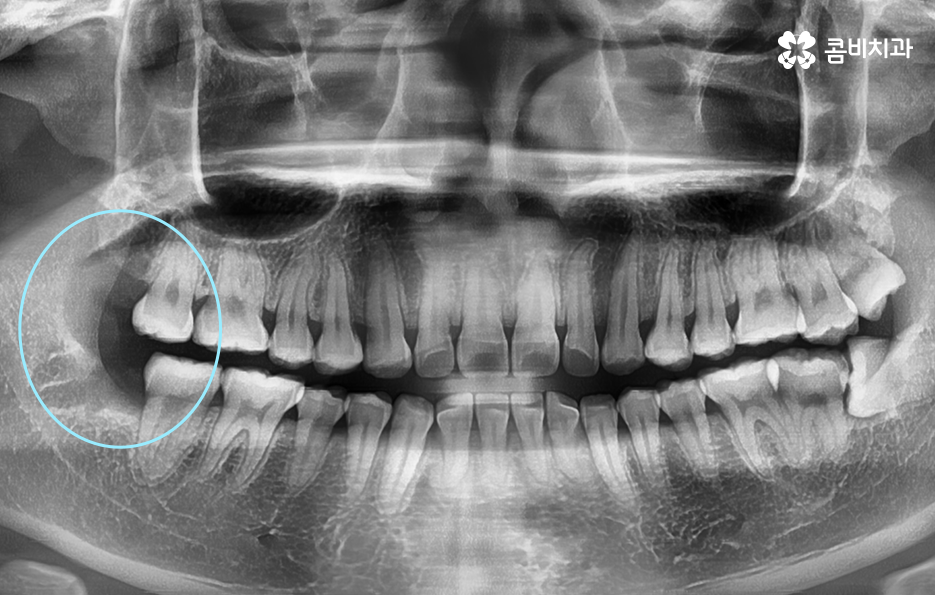

사랑니 발치에 있어서 사랑니가 충치로 인해 썩었거나 현재 잇몸이 붓고 염증이 발생한 상황과 같이 특정 상황적 조건을 무시하고 사랑니의 모양만을 두고 발치 난이도를 구분해보자면 당연하게도 정상적으로 맹출된 사랑니가 보다 뽑기 쉽다고 할 수 있겠고 반면에 완전 매복되어 있는 사랑니의 경우 보다 발치의 어려움을 느낄 수 있는데요

위 환자분의 사랑니 케이스를 살펴보면 윗니의 경우 정상 맹출된 사랑니의 형태를 보이지만 아랫니의 경우에는 부분 매복되어 있고 누워서 자라고 있는 사랑니의 형태를 볼 수 있어요. 다 그런 것은 아니지만 윗니의 경우 중력에 의해 정상 맹출된 사랑니의 형태가 좀더 많다면 아랫니의 경우 매복사랑니의 형태가 많은 편이기 때문에 하악 사랑니의 발치가 좀더 어려운 경우가 있어요